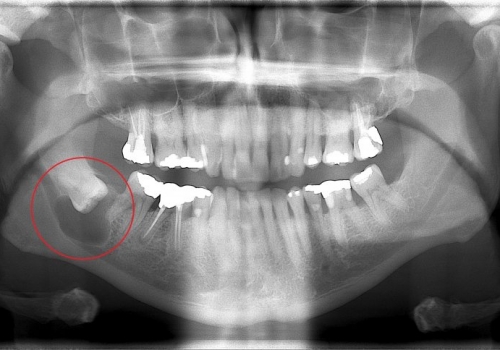

Normal halda insanın diş sırasında hər çənədə iki ədəd olmaqla, ümumilikdə dörd agıl dişi mövcuddur. Ağıl dişinin çıxması bəzi şəxslərdə heç bir kliniki əlamət və ya şikayətə səbəb olmasa da, bir çox hallarda müəyyən kliniki əlamətlərlə öyünü biruzə verir. Bu əlamətlər əsasən çənənin arxa tərəfində təzyiq, çənəni açıb baglama əsnasında agrı və məhdudlaşma kimi özünü göstərə bilir. Bu hallarda mütəxəssis konsultasiyasının önəmi olduqca böyükdür. Belə ki müayinə zamanı cərrah-stomatoloq kliniki və radioloji dəyərləndirmə apararaq dişin dogru pozisiyada yerləşib yerləşmədiyi, dişləmə çıxma ehtimalını, agıl dişinin çənəyə görə ölçüsü və çənə darlıgı kimi durumları dəyərləndirərək tətbiq edilməli olan müalicə taktikasını müəyyən edir.